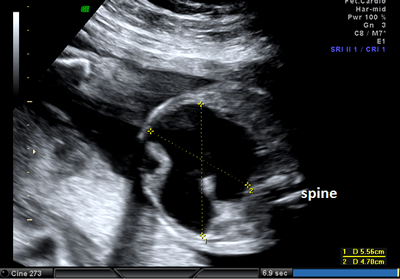

A 26-year-old pregnant women, gravida 1, para 0, was admitted to our prenatal diagnosis centre for detailed ultrasonography examination. Obstetric history was unremarkable. A single fetus was detected at 26 gestational weeks. A presacral located cystic mass measuring 45 × 55 × 40 mm was seen on ultrasound examination (Fig. 1). On doppler ultrasound, the cystic structure with both umbilical arteries around was considered an enlarged distally obstructed fetal bladder initially (Fig. 2). However, the bladder was later identified more superiorly. The amniotic fluid index was 129mm. Diagnosis of the cystic mass was unclear and a fetal MRI was performed, which delineated a large cystic mass with minimal internal echogenicity area, the type IV teratoma (big arrow head). The white arrow demonstrates a cystic mass considered as a hydrometrocolposis (Fig. 3).

Figure 2: The cystic structure with both umbilical arteries around. |